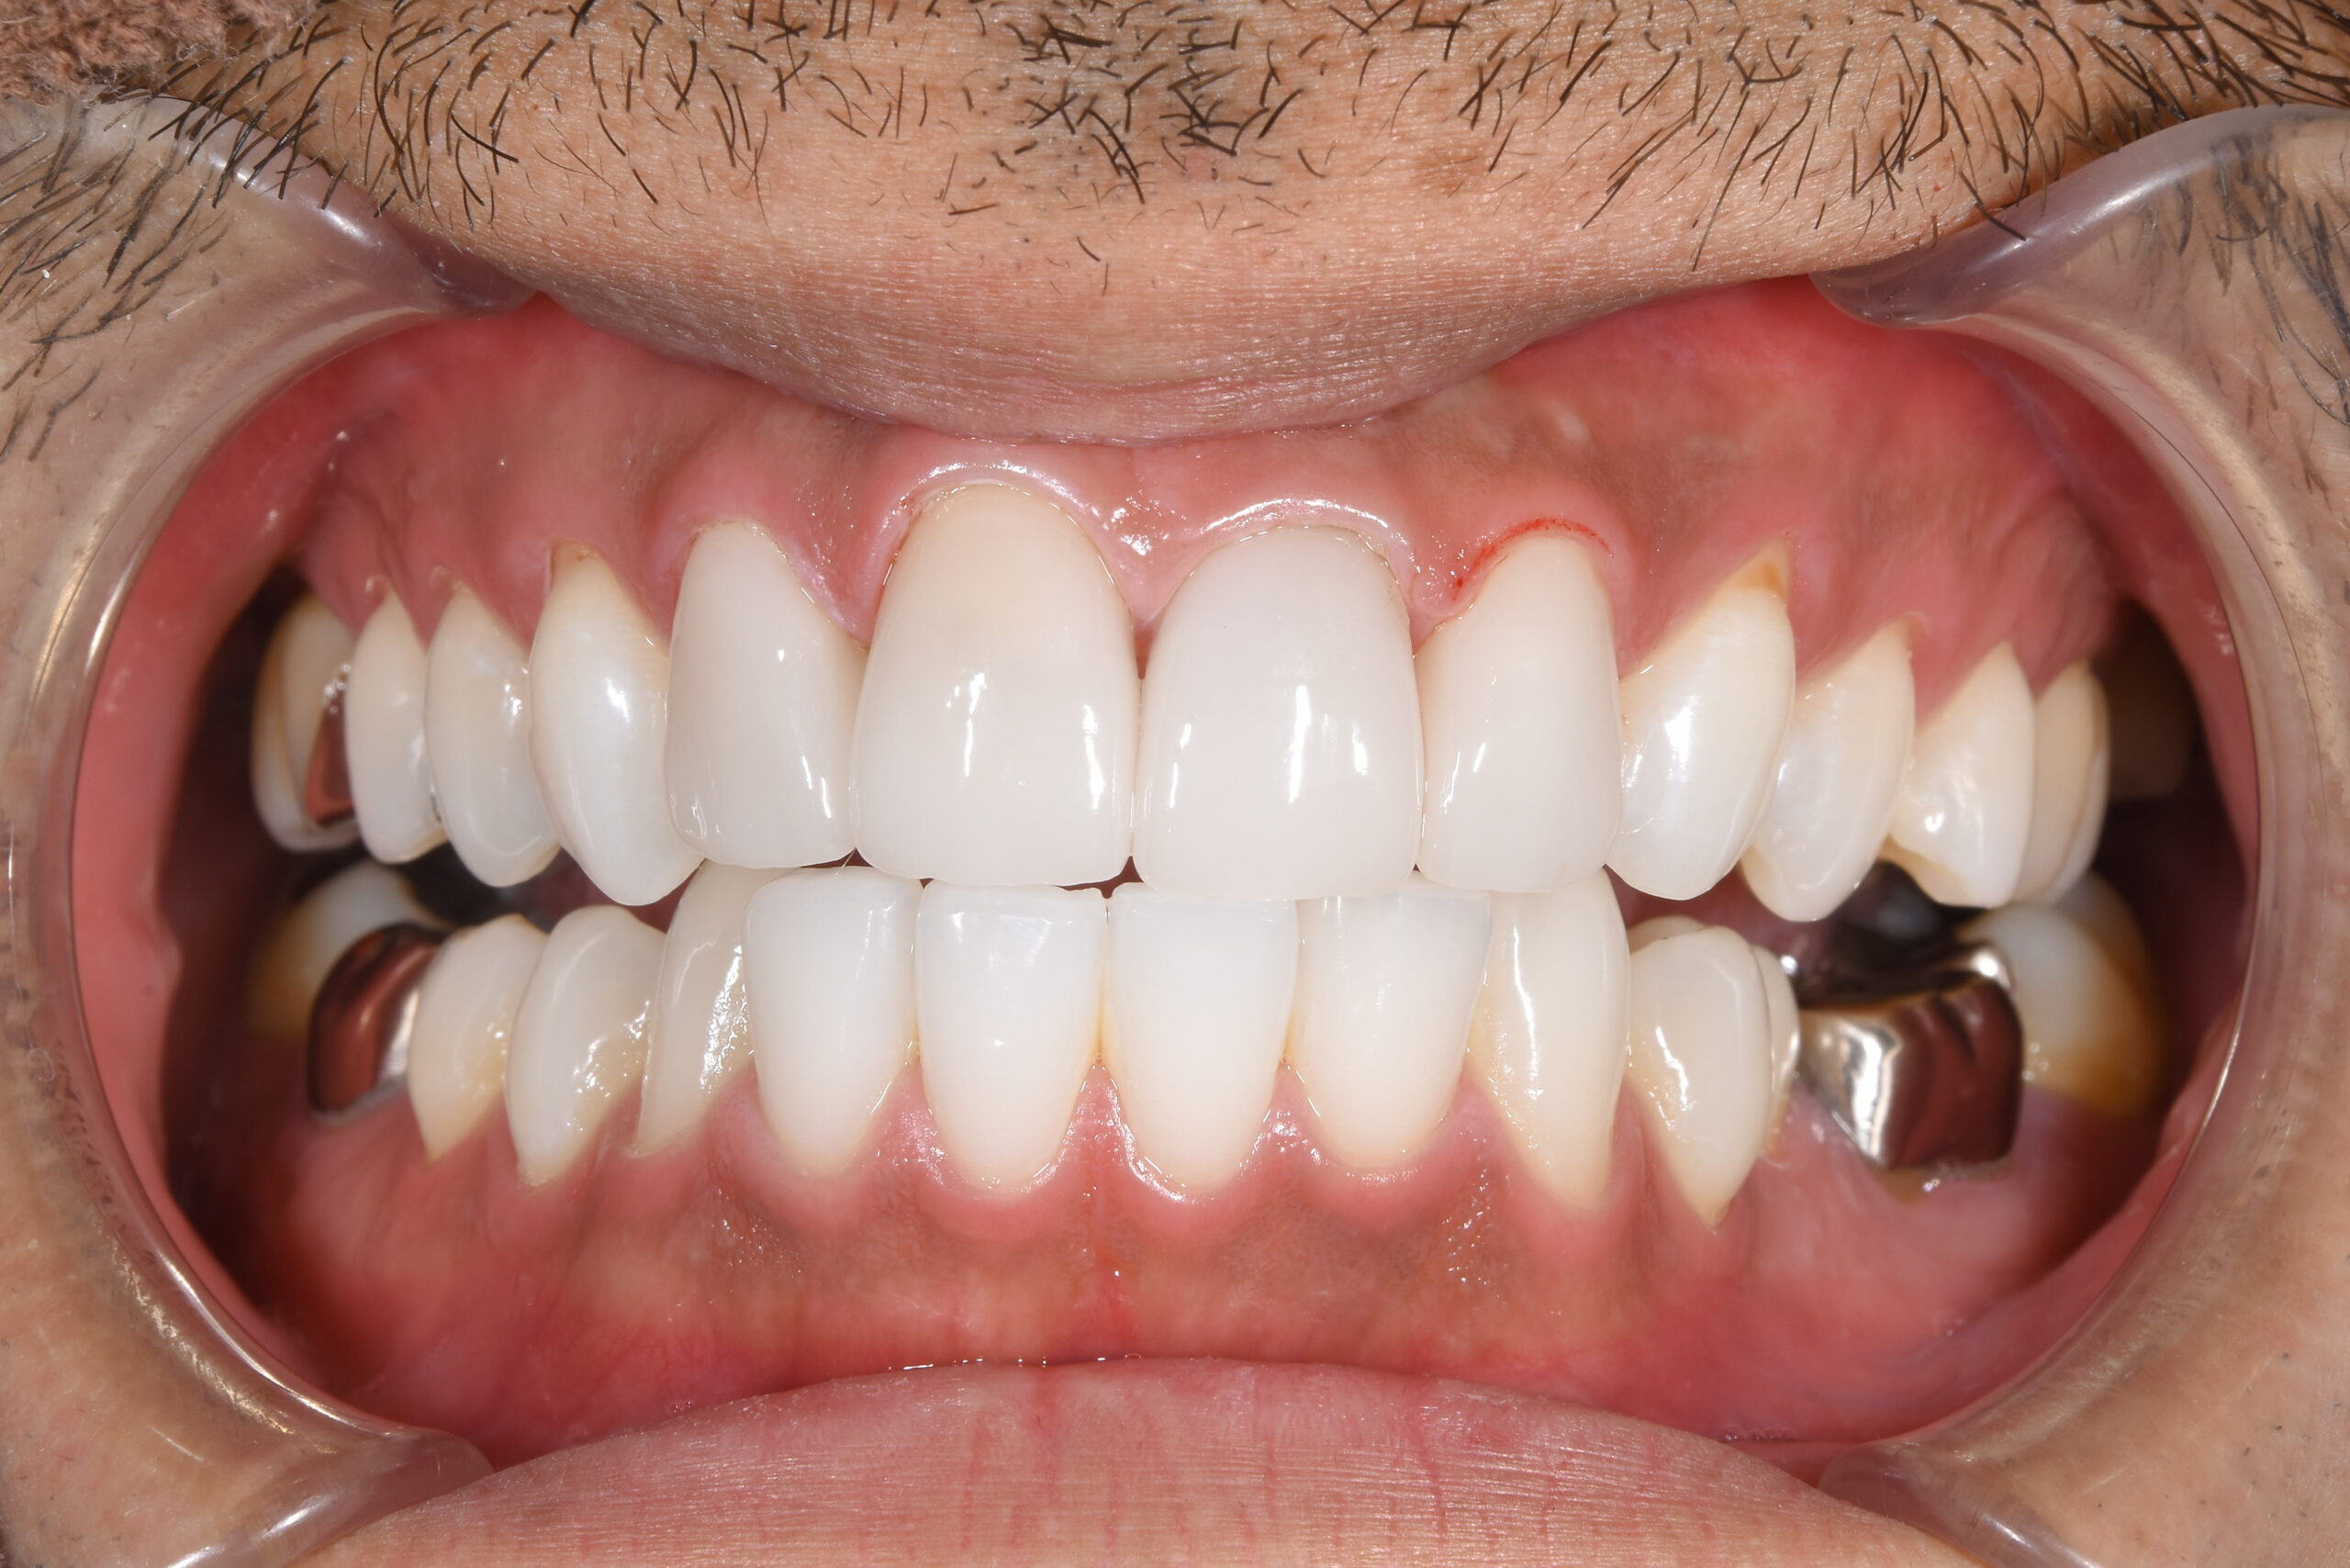

矯正治療とセラミックでの全顎治療の1例